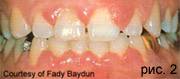

Эта форма гингивита связана с половыми гормонами, и поэтому встречается в пубертатный период (полового созревания), беременности(рис.2), а также после орального приема контрацептивов или при стероидной терапии на фоне хронического простого гингивита, характеризующегося приступообразными обострениями.